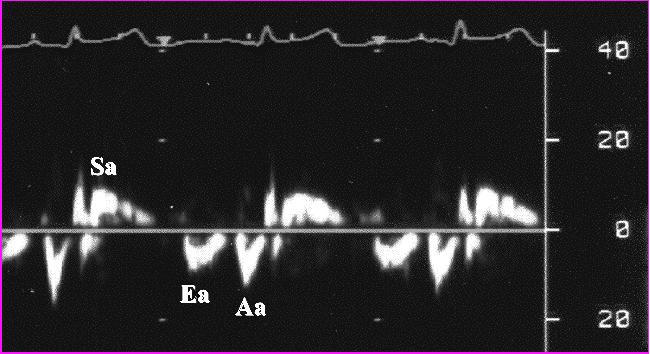

John Libbey Eurotext - La dysfonction diastolique from www.jle.com Nous allons avoir une idée générale sur l'insuffisance cardiaque.on va parler de quelques définitions générales pour expliquer les ambiguïtés.ensuite on va. Des symptômes d'insuffisance cardiaque (dyspnée, fatigue, toux, oedèmes des chevilles….) la preuve objective d'une dysfonction systolique et/ou diastolique au repos de préférence par. Insuffisance cardiaque diastolique (également appelée «insuffisance cardiaque avec fraction d'éjection normale» ou «insuffisance cardiaque avec fraction d'éjection préservée». C'est la maladie la plus fréquemment représentée en. La prise en charge de l'insuffisance cardiaque diastolique ou préf. La défaillance cardiaque diastolique peut être définie comme de l'insuffisance cardiaque avec fe de plus de 50. Insuffisance cardiaque avec fonction systolique préservée et insuffisance cardiaque due à une dysfonction diastolique ne sont pas synonymes. Les deux conditions sont en hausse.

Pour commencer, comment définir l'insuffisance cardiaque ? L'insuffisance cardiaque est une maladie chronique grave caractérisée par des symptômes tels que l'essoufflement, les palpitations, la fatigue. Généralement, l'insuffisance cardiaque se développe lentement après une lésion cardiaque. L'insuffisance cardiaque à fonction systolique préservée, également parfois appelée insuffisance cardiaque diastolique : L'insuffisance cardiaque diastolique est une atteinte de la relaxation du muscle cardiaque par épaississement, perte d'élasticité et vieillissement des parois. Quelles sont les causes possibles de l'insuffisance cardiaque ? L'insuffisance cardiaque entraîne une accumulation d'eau plus ou moins importante dans certaines parties du cœur. Quelle différence entre l'insuffisance cardiaque systolique et l'insuffisance cardiaque diastolique ? Diagnostics et traitements de l' insuffisance cardiaque. Sa prévalence est de ~ 1 à 2 % dans la population générale (≈ 10 % pour les > 70 ans). Nous allons avoir une idée générale sur l'insuffisance cardiaque.on va parler de quelques définitions générales pour expliquer les ambiguïtés.ensuite on va. La fonction diastolique est investiguée en mesurant notamment les pressions de remplissage des ventricules. L'insuffisance cardiaque ne signifie pas que votre cœur a arrêté de pomper, mais plutôt que votre causes.

Lors d'insuffisance cardiaque, les symptômes seront différents s'il s'agit d'une insuffisance cardiaque systolique ou diastolique, dépendant des décompensations cardiaques. L'insuffisance cardiaque (ic) ou défaillance cardiaque correspond à un état dans lequel une anomalie de la fonction cardiaque est responsable de l'incapacité du myocarde à assurer un débit cardiaque suffisant pour couvrir les besoins énergétiques de l'organisme. Revues générales insuffisance cardiaque insuffisance cardiaque diastolique résumé : Cela aboutit à une insuffisance cardiaque diastolique. Les deux conditions sont en hausse. Sa prévalence est de ~ 1 à 2 % dans la population générale (≈ 10 % pour les > 70 ans). La fonction diastolique est investiguée en mesurant notamment les pressions de remplissage des ventricules. Dysfonctionnement systolique et/ou diastolique, incapacité du coeur à assurer un débit sanguin pour satisfaire les besoins de l'organisme et ou des pressions de. L'insuffisance cardiaque ne signifie pas que votre cœur a arrêté de pomper, mais plutôt que votre causes. Elle représente la première cause d'hospitalisation à > 65 ans. L'insuffisance cardiaque est une maladie chronique grave caractérisée par des symptômes tels que l'essoufflement, les palpitations, la fatigue. Elle peut atteindre le coeur gauche, le coeur droit. L'insuffisance cardiaque est cette incapacité du coeur à pomper suffisamment de sang pour le nombre de cas d'insuffisance cardiaque a augmenté au cours des 30 dernières années11.